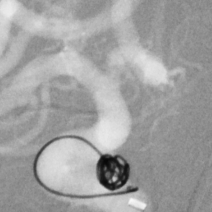

啥也别说了,赶紧去做脑血管造影备治疗吧,结果发现颅内一个炸弹💣(颅内动脉瘤),而且长在一个不太容易破裂的部位(床突旁),形状也不太规则,上面还有一个细长的小泡(破裂点),破裂机制:这个破裂小口,多次小量出血,通过反复的脑脊液循环大部集聚到了腰大池,出现了颅内几乎看不到啥异常而腰大池内为血性不凝脑脊液的巨大反差,血液在蛛网膜下腔进一步刺激神经根,才导致了脖子疼和腰疼~~~,但是,这是脑动脉瘤反反复复破裂出血导致的哦,细思极恐………

这个患者是幸运的,毕竟最后找到了颅内潜伏的炸弹,微创手术顺利拆除,消除了再次出血的风险。